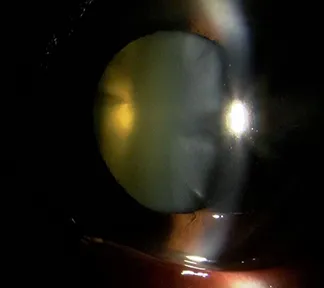

白内障は目の中の水晶体が濁って視力低下を起こす病気です(写真1)。白内障手術はその濁りを取り除き、代わりに人工のレンズを目の中に入れる手術です(写真2)。

また当院では、さまざまな白内障に対応いたします。下にお示しする症例は、非常に進行した白内障の手術前後の写真です。